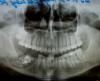

НаталиКМ Опубликовано 26 ноября, 2009 Поделиться Опубликовано 26 ноября, 2009 Здравствуйте!!!При проведении цистотомии были удалены 7, 6, 5 зуб (киста больших размеров) два раза в неделю меняют йодные турунды. После операции прошел месяц, врач говорит, что ещё месяц нужно будет менять турунды и всё заживет. Хотелось бы узнать, грозит ли мне повторная операция Цистэктомия мой врач по этому поводу молчит, может, не хочет меня расстраивать…или пока рано по этому снимку судить…Снимок выполнен месяц после операции. Ссылка на комментарий